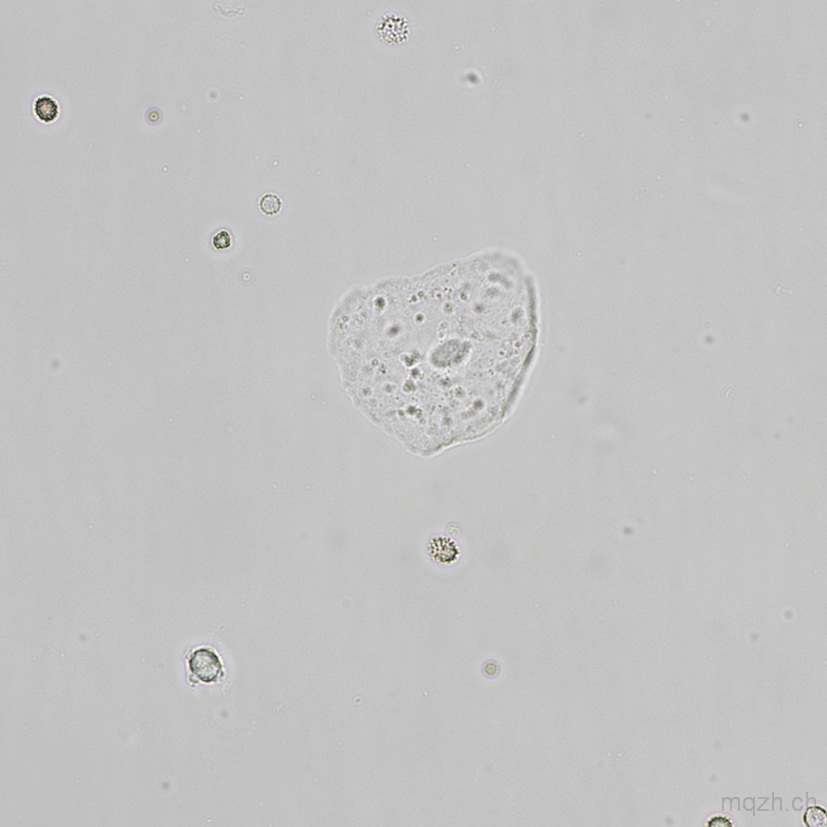

MQ 2025-4 Urinary Sediment U4